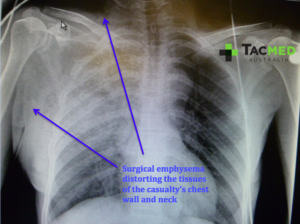

In the case study above, where a penetrating injury has caused a hole in the side of the chest cavity and damaged the underlying lung, a few things occur to disrupt the normal breathing mechanism. First, the adhesion between the lung and the inside of the chest wall is lost by entry of air into that space and the lung collapses down like a popped balloon, in a condition known as pneumothorax. This collapse can be partial or complete in the damaged lung, with the immediate effect on the casualty being a reduction in the lung volume available to get oxygen into their system. Fortunately the human body has an amazing amount of redundancy and can function quite well on one lung, as seen in the case study above. Pneumothorax is often seen in the civilian trauma context following blunt trauma such as a car crash, where injuries such as broken ribs can internally puncture the lung and cause it to collapse.

The final life-threatening chest injury that I will discuss in this article, and in my opinion the most important for a first-responder to be aware of, is tension pneumothorax. Tension pneumothorax occurs when air leaking internally from a damaged lung accumulates between the inside of the chest wall and the damaged lung, gradually building up pressure with every breath until the amount of air trapped in one side of the chest starts to push on the heart and the undamaged lung. Left untreated, the pressure from this trapped air will collapse the undamaged lung and kink off the major blood vessels to and from the heart, leading to a situation where the casualty cannot breathe and has minimal output from their heart, eventually causing death. Anyone who has seen the classic film “Three Kings” will have seen a graphic representation of tension pneumothorax after Mark Wahlberg’s character gets shot through the chest. The scene is actually a decent depiction the “air hunger” and anxiety that a casualty with a tension pneumothorax displays as pressure accumulates. In the scene George Clooney puts his ER skills to good use by correctly diagnosing and treating the tension with a procedure known as needle thoracocentesis (Ice Cube doesn’t add any real value!).

Whilst tension pneumothorax is more often seen in penetrating chest injuries, it can certainly be seen following blunt, or other forms of chest trauma including dive injuries. Tension pneumothorax can also occur after a sucking chest wound has been treated with an occlusive dressing, or if a vented seal has been used and the vent has become clogged with dried blood. In that setting it is reasonable to peel the dressing back and see if pressure vents from the wound in the chest, before resealing the wound or decompressing the chest with a needle if the tension remains unresolved. Furthermore, for anyone who does aeromedical evacuation, any patient with a pneumothorax on the ground must be monitored closely when taken to altitude, especially in unpressurised aircraft. As the casualty gains altitude, any trapped gas inside their body will expand due to reduced atmospheric pressure. If gas is trapped within the chest cavity, as in pneumothorax, then as it expands it can cause tension. If the situation allows, it is ideal to place chest tubes in casualties with a suspected pneumothorax before aviation medical evacuation (AME), however if you’ve got to get back in the air quickly then have the needle at the ready!

The following X-rays show the normal chest anatomy labeled in the first image, and a tension pneumothorax seen in the second image. The distortion of the anatomy caused by the pressurised air can be seen and it can be appreciated that air entry into the undamaged lung will be reduced, and blood flow to and from the heart will be compromised. Those in the medical profession will recognise this second X-ray as “the X-ray that should never be taken” meaning that the condition should ideally have been recognized clinically and treated without burning time getting an X-ray done.